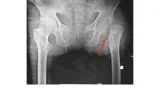

明日手術予定の大腿骨転子部骨折の患者さんが嘔吐しているとのこと,

鎮痛目的で処方していたロキソプロフェンを中止するよう指示しました.

朝, 電話をいただいた患者さんの状態を確認しましたが, 特に問題なく, 明日の手術予定はそのままに.

血糖コントロールが不良の大腿骨転子部骨折の患者さんは, まだ血糖が高い時間があり, さらにインスリン投与量を増量するように指示しました.